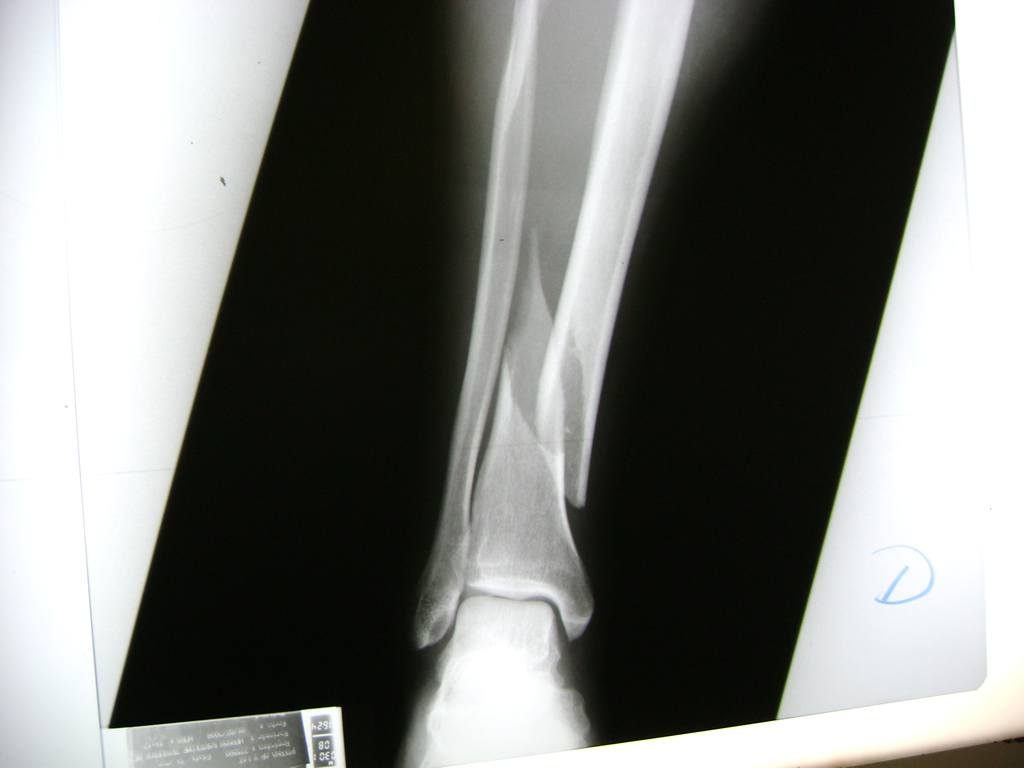

Cirugías de Peroné y Tibia

La mayor parte de las roturas implican a la parte proximal del hueso (parte del hueso próximo a la rodilla) o a la parte distal (parte del hueso cerca del tobillo).

Debido a la fina cobertura de piel que recubre la tibia y el peroné, las fracturas generalmente son abiertas, es decir, el hueso roto rasga la piel, atravesándola. Las fracturas de tibia y peroné generalmente se producen por un fuerte impacto o torsión.